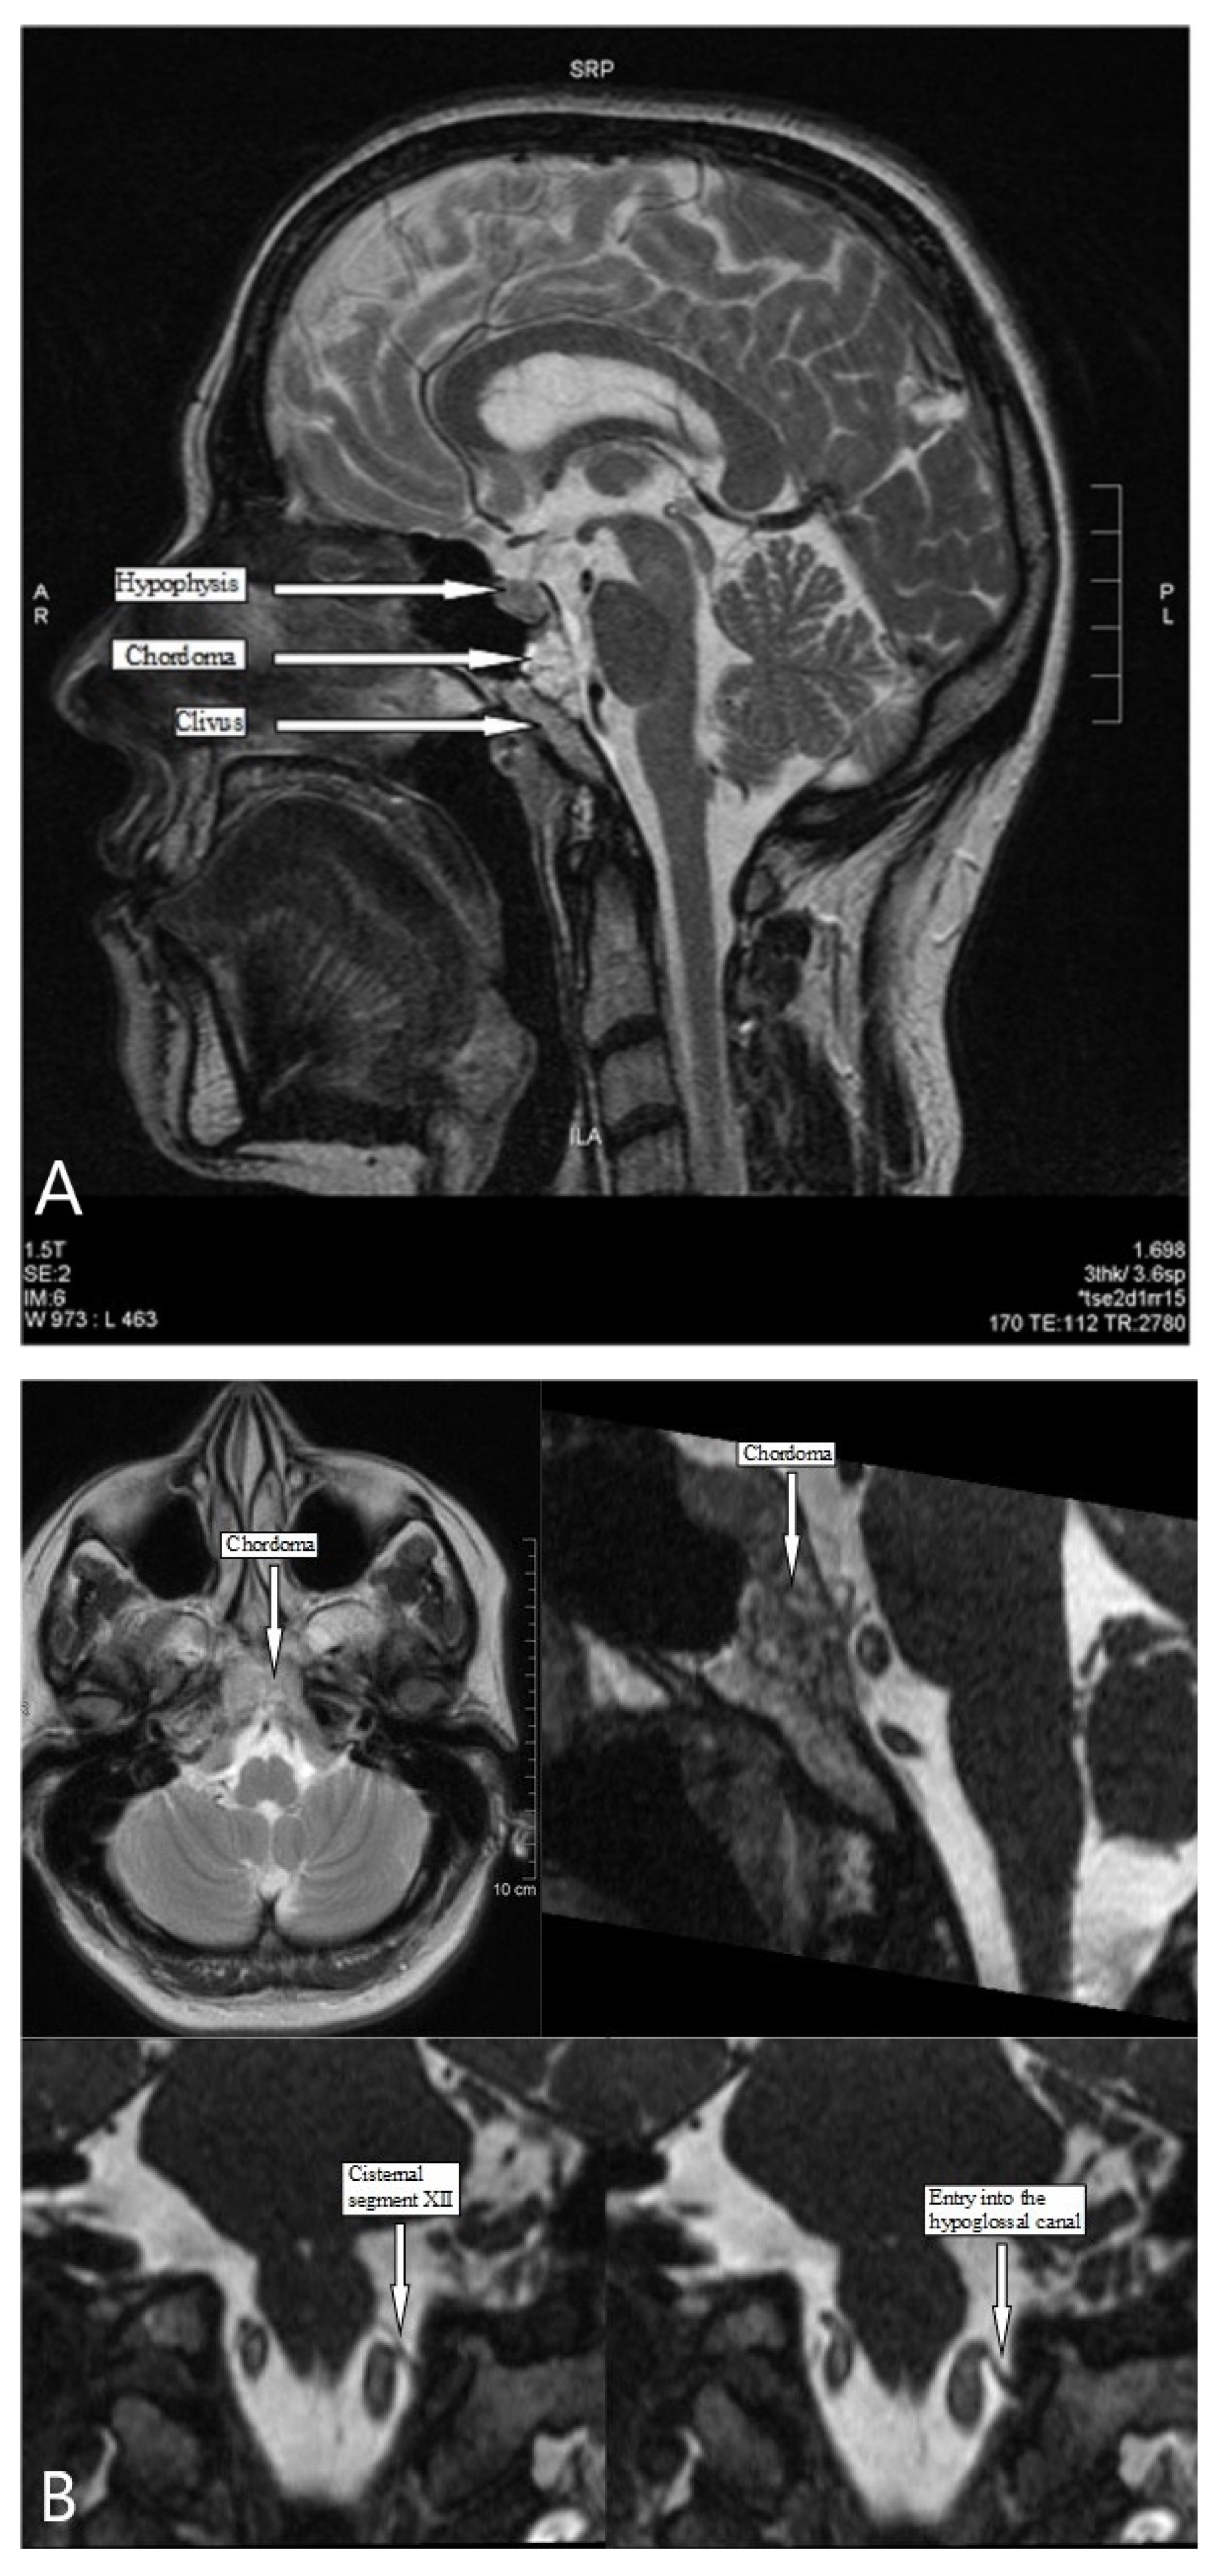

2.1. Clinical Findings and Imaging

- Alharbi, F.A.; Lenarz, T.; Stoever, T. A case of unilateral hypoglossus nerve palsy associated with chordoma in the region of clivus. Eur. Arch. Oto-Rhino-Laryngol. 2009, 266, 2001–2003. [Google Scholar] [CrossRef] [PubMed]